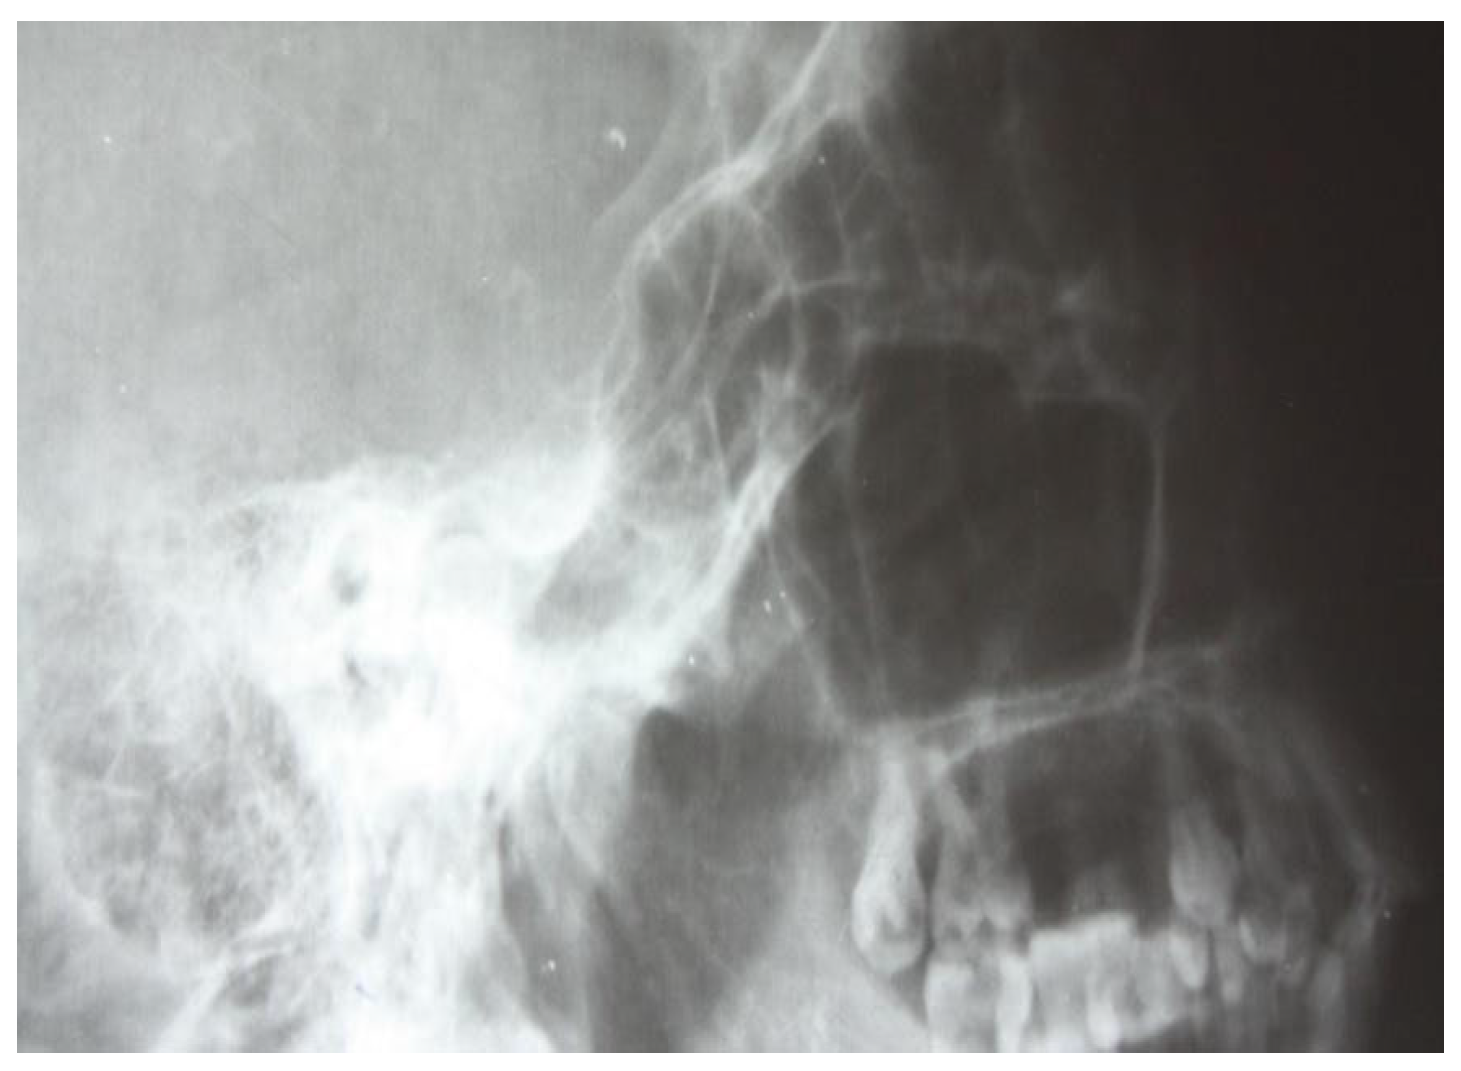

3.1.1. Conventional Radiology